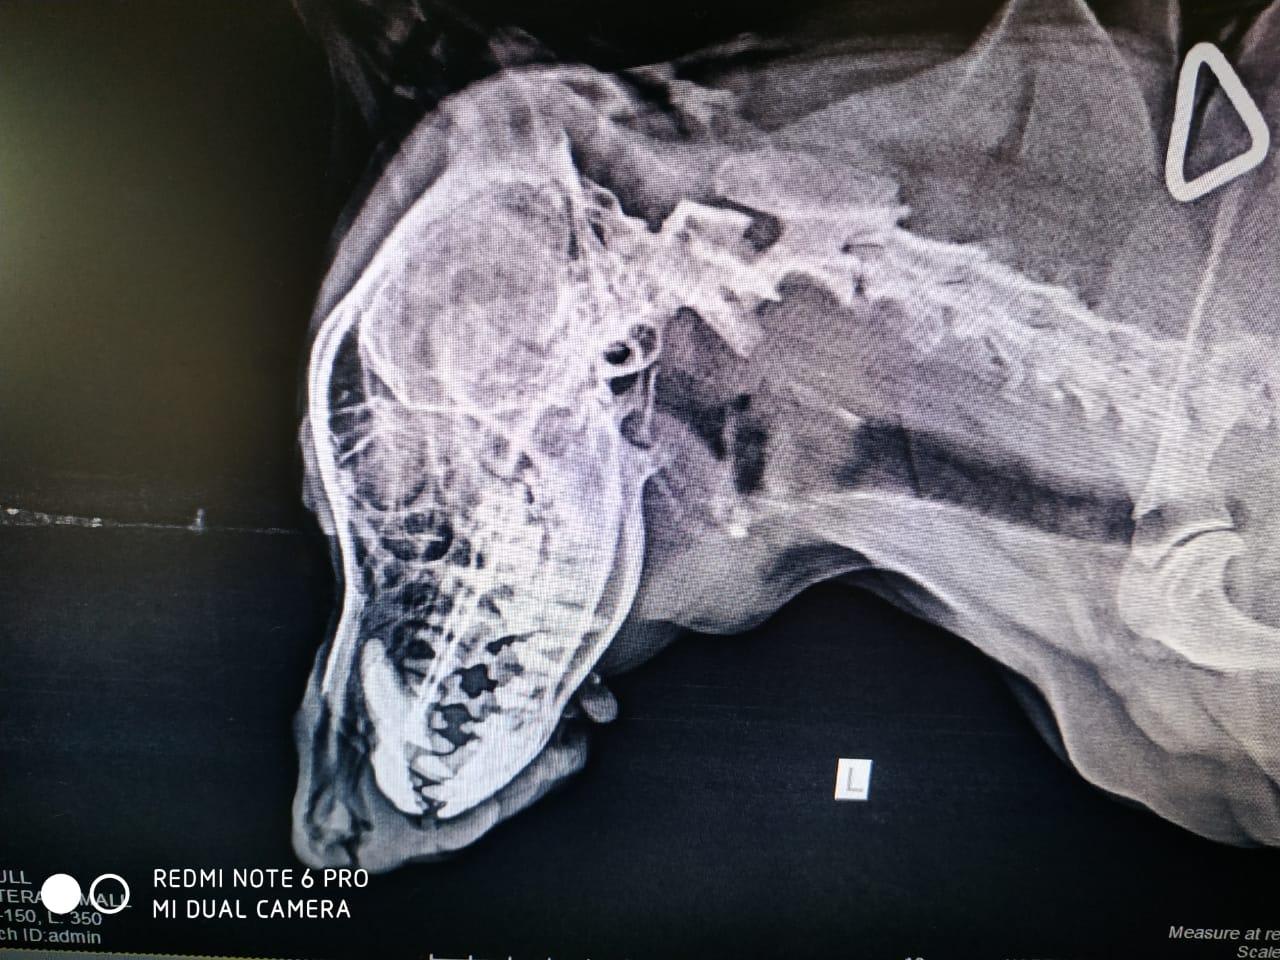

Tiny have left jaw pain local veterinary dr has told it may be a tooth pain so he gave pain killers for 5 days that time pain has stopped but now after dose he has started moaning . Plz suggest a proper treatment or available treatment options.Attached is x-ray and fnac report for tiny.

If it is tooth pain I would consider antibiotics as it may be an underlying infection. I would recommend dental xrays if a veterinarian has that available. They are better to evaluate the teeth then a skull xray as it focuses on each spot individually. Thank you for using Petco Pet Education Center, formerly Petcoach.